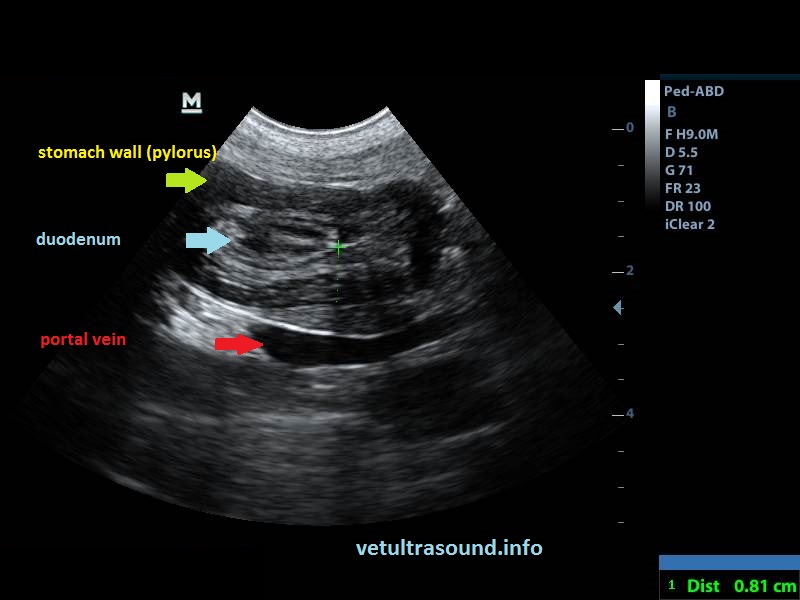

Ευρήματα: Διάταση του στομάχου με υγρό περιεχόμενο και αέρα. Εγκολεασμός του δωδεκαδακτύλου μέσα στον πυλωρό. Αύξηση της ηχογένειας του μεσεντερίου λίπους περιφερικά του εγκολεασμού. Ήπια διόγκωση των μεσεντέριων λεμφαδένων με αντιδραστική ηχομορφολογία.

Findings: Marked distension of the stomach with fluids and air. Intussusception of the duodenum to the pylorus. Increased echogenicity of the mesenteric fat around the intussusception. Mild enlargement of the jejunal lymph nodes with reactive echotexture.